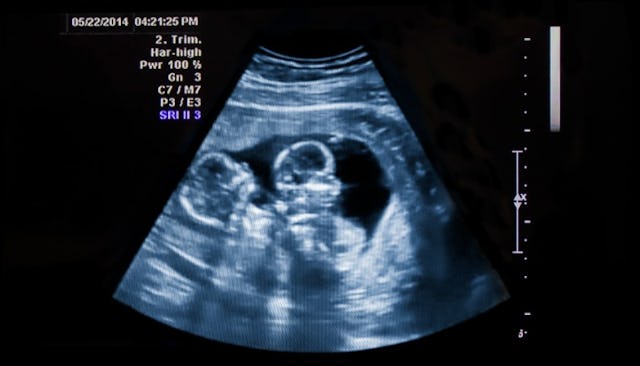

Oh, I remember it well. My husband and I were at my 20-week ultrasound excitedly and anxiously awaiting the gender reveal of our third child. A couple minutes into my appointment after finding out we were having a boy (as I had expected), I jokingly asked the ultrasound technician, “There’s just one in there, right?” I had been paranoid, but in my mind, I believed it was needlessly so. The tech quickly confirmed. Then she moved the wand to the other side of my belly. That’s when her face just changed. I looked at her and knew something was wrong. I abruptly asked, “What?!”

It turned out there was another baby in there. Everything after that is kind of blurry. I felt disbelief and looked at my husband in panic. He was expressionless. Then I remember saying, “No, no, no, no,” and asking the technician if she was joking. I 100-percent expected her to admit that she was kidding, but who would joke about such things?! After telling me that it was, in fact, not a joke, she excused herself so I could freak out in privacy. I took some time to panic and cry and say God-knows-what before we left—having to inevitably reschedule my appointment for a longer time slot.